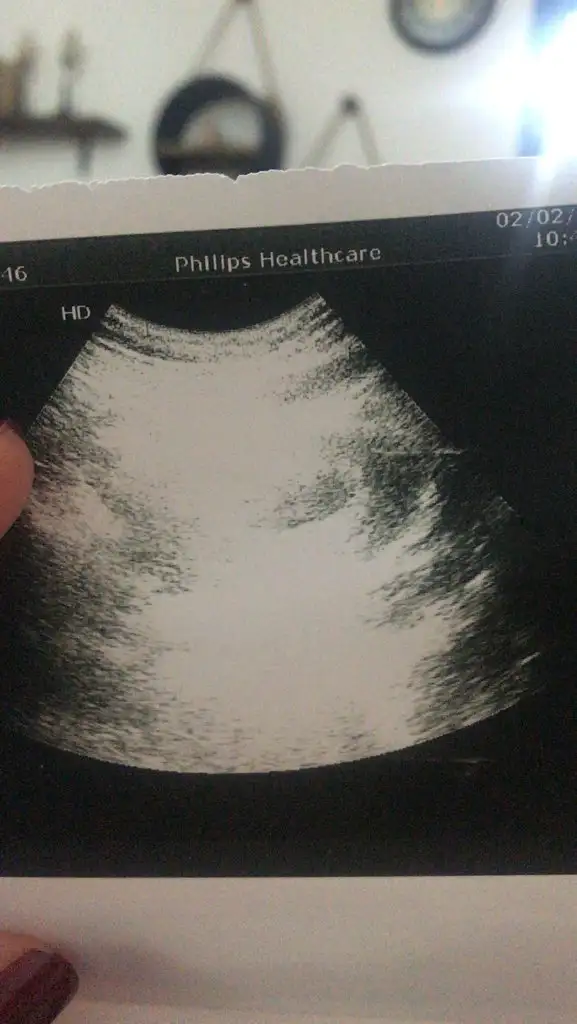

Bana da bakabilir misiniz acaba rica etsem 🌸 karından bakıldı burada

Eklentiler

• D1E339F0-6322-4CD1-8EF3-0F4FDB940F4E.webp

D1E339F0-6322-4CD1-8EF3-0F4FDB940F4E.webp

19,6 KB · Görüntüleme: 120